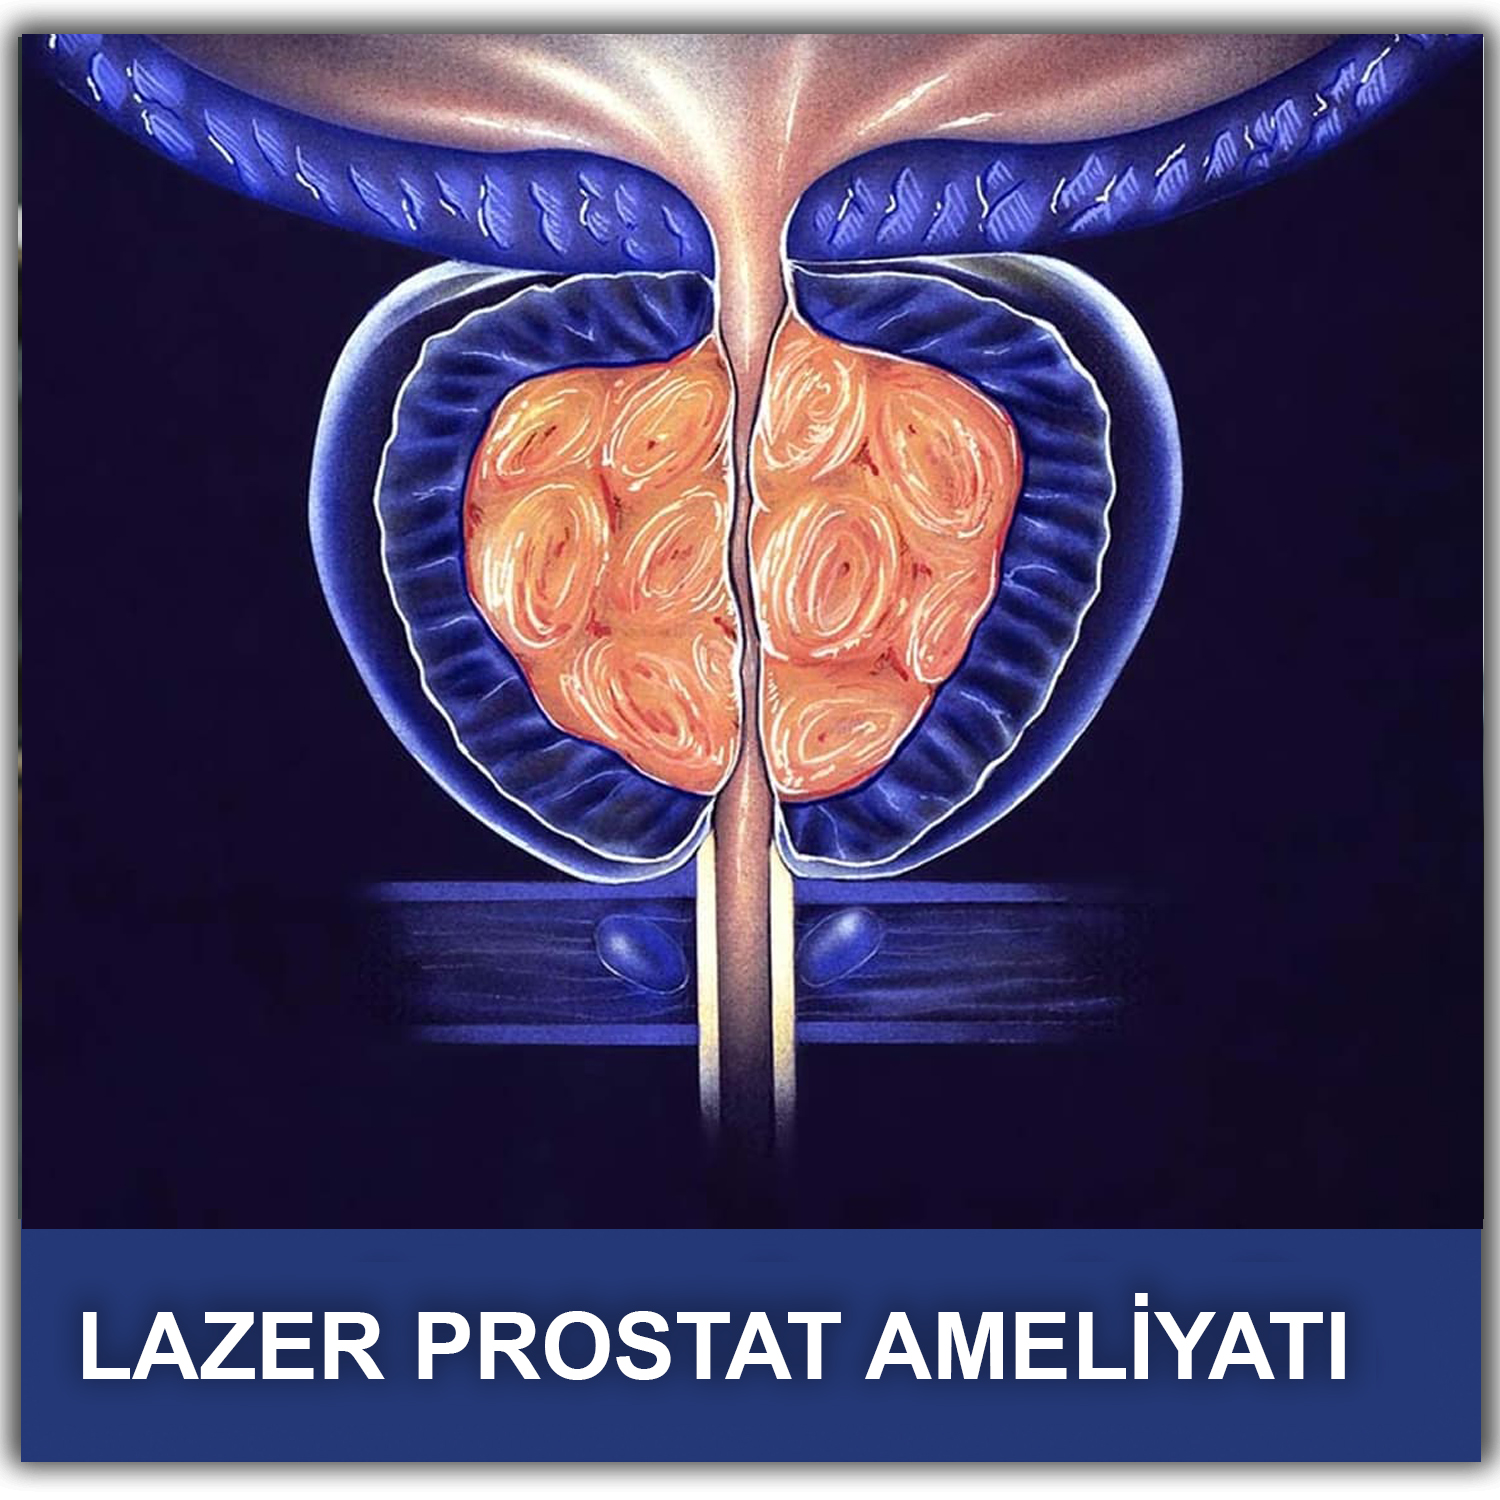

Простата, обычно ассоциируемая с мужским здоровьем после полового созревания, также присутствует у детей, хотя и в значительно меньших размерах. Этот орган, расположенный под мочевым пузырем и окружающий уретру, играет роль в выработке жидкости, которая составляет часть семенной жидкости. Несмотря на то, что проблемы с простатой у детей встречаются редко, понимание её развития и потенциальных патологий важно для ранней диагностики и лечения.